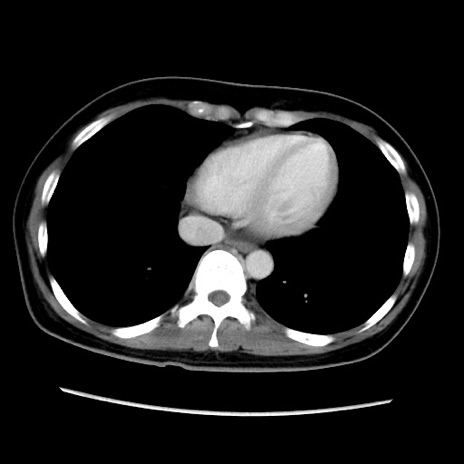

症例39(横断像)

【症例】40歳代女性

【主訴】上下腹部痛

【現病歴】2日目から下腹部痛あり。夜間は痛みで眠れなかった。昨日より上腹部痛と下痢が出現。臥位で痛みは軽快したため、休んでいた。本日になって臥位でも立位でも痛みが強くなってきたため救急要請。

【既往歴】子宮内膜症

【身体所見】部:平坦・軟、左上下腹部に圧痛あり、反跳痛あり。

【データ】WBC 21800、CRP 26.78